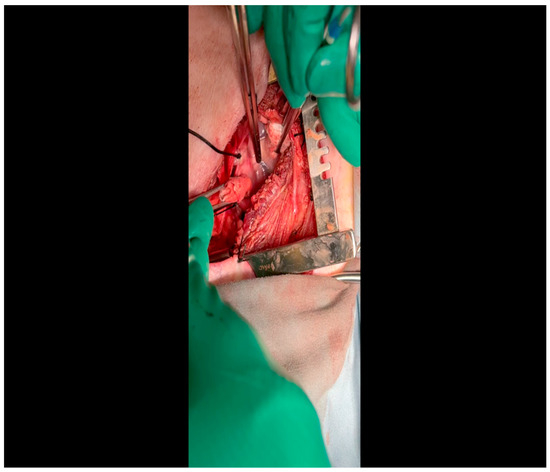

- Electrocautery is used to cut through the skin and muscle of the chest wall. A Weitlaner retractor is used to retract the muscle. The intercostal muscles are divided just above the 3rd or 4th rib (Figure 2), and a Kelly clamp facilitates entry into the parietal pleura and protects the underlying intrathoracic structures as the incision is enlarged; finally, a rib spreader is placed to open the incision.

- The pericardium is opened (Figure 3) with scissors. It is important to identify and protect the phrenic nerve.

- A sternal retractor is placed to separate the rib cage and expose the heart.

- The pericardium is opened with Metzenbaum scissors.